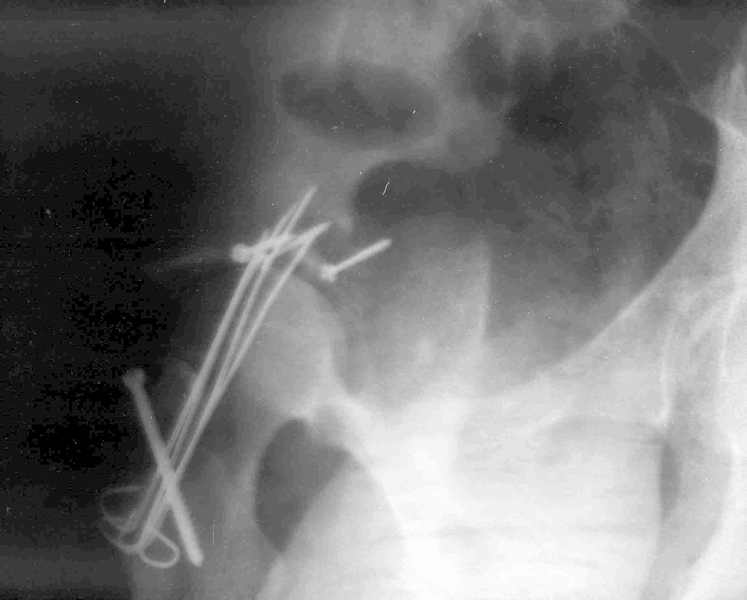

Мужчина 32 года, автотравма 6 недель назад. При поступлении был установлен диагноз "Ацетабулярный перелом". Вывих бедра не был установлен.

После установления вывиха бедра через 3 недели после травмы больному выполнена попытка открытой репозиции, остеосинтез вертлюжной впадины, Бедро фииксировано трансартикулярно спицами. После операции неврит седалищного нерва. В течение ещё 3-х недель после операции установлено что отломки не репонированы, вывих бедра не устранён (см. КТ и рентгенограмму), неврологической динамики нет. Возние вопрос о повторном оперативном вмешательстве по поводу чего разгорелись жаркие споры и сформировалось следующие мнения:1. Тотальное эндопротезирование с цементной фиксацией чашки протезом "ЭСИ" (другого протеза нет)2. Повторная открытая репозиция бедра с замещением дефектов вертлюжной впадины аутокостью с целью подготовки для последующего эндопротезирование. Предполагается фиксация тазобедренного сустава в послеоперационном периоде гипсовой повязкой или аппаратом внешней фиксации.Прошу высказать ваше мнение о тактике дальнейшего лечения пациента, о предложенных вариантах. Отдельный вопрос о возможности первичного тотального эндопротезирования при ацетабулярных переломах. (Лечащий врач настаивал перед первой операцией на выполнении тотального эндопротезирование с цементной фиксацией чашки через 3 недели после травмы)

Было бы существенным посмотреть обзорную R-грамму до операции. По данным послеоперационных снимков и КТ имеется низкий двухколонный перелом или

высокий Т-образный перелом с отрывом свода. Для уточнения необходиы косые проекции (Judet). Весь ли седалищный нерв молчит или только м/б порция?

Xray1

Xray2

Высылаю прямой обзорный и косой подвзошный снимки, косой запирательный неудовлетворительного качества.